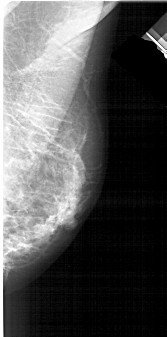

A_1938_1.RIGHT_MLO

RIGHT_MLO LINES 4711 PIXELS_PER_LINE 2326 BITS_PER_PIXEL 12 RESOLUTION 43.5 NON_OVERLAY